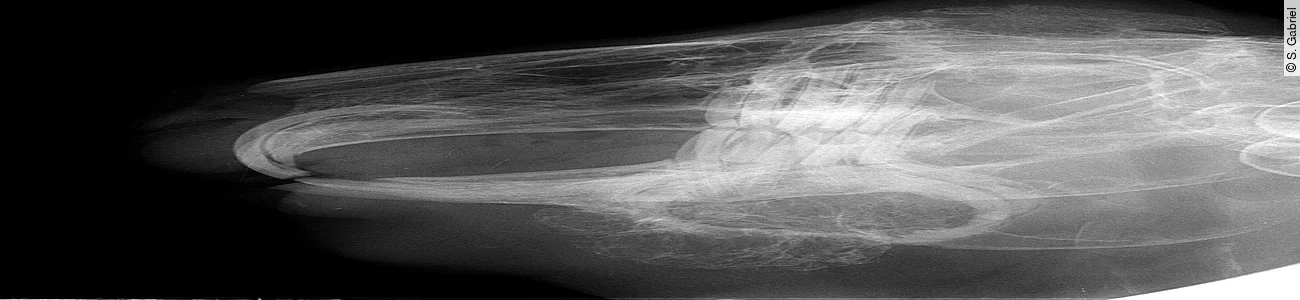

Ausgehend von einer Zahnwurzelentzündung (etwa durch unsachgemäßes „Abknipsen“ oder durch parodontal eingespießtes Fremdkörpermaterial, wie z. B. hölzerne Pflanzenfasern) kommt es zur eitrigen Alveolitis, die ihren Ausgang – der Schwerkraft folgend – nach ventral sucht, wenn der Zahn noch in der Alveole festsitzt. Osteolyse und Osteomyelitis durch pyogene Bakterien reizen den Körper zu einer fulminanten Entzündung mit Bildung einer dicken Demarkation, der sog. pyogenen Membran. Parallel zu lytischen Prozessen, die die Spongiosa des Unterkieferknochens auflösen ([Abb. 1]), kommt es zu stabilisierenden Knochenauftreibungen durch eine periostale Reaktion, oft mit blasenförmiger Auftreibung ([Abb. 1 a] und [1 b]) und in Form von radspeichenartigen Spiculae des Periostes ([Abb. 1 c]).

Abb. 1a-c